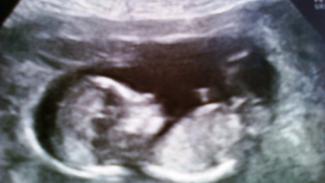

Výsluch z 1. novembra obsahuje aj svedectvo dvoch pôrodníckych expertov, doktora Roberta Slotnicka a doktorky Stacy Mellumovej. Lekári rozprávali o rizikách tehotenstva a pôrodu, ktoré Elise hrozia, a to hlavne v spojitosti s jej epilepsiou. Elisin stav si totiž vyžaduje lieky proti záchvatom, ktoré však v tehotenstve môžu mať negatívny dopad na plod. Lekári sa taktiež zhodli na tom, že tehotenstvo by dokonca mohlo znížiť účinnosť týchto liekov.

Doktorka Mellumová svedčila v prospech Elisiných rodičov, ktorí si želajú, aby donosila dieťa. Následne by ho dali na adopciu. Podľa doktorky je štandardný medicínsky postup v prípade vysoko rizikového tehotenstva epileptikov dôkladné monitorovanie a správne nastavenie dávok liekov, nie potrat.

Návrh doktora Slotnicka o interrupcii pre Elisu je radikálna odluka od odporúčania Americkej akadémie pôrodníkov a gynekológov (ACOG). V nich sa uvádza, že ak postihnutá žena je tehotná, malo by sa zahájiť vyšetrovanie, na základe ktorého by sa zistilo, či došlo k zneužitiu ženy. (V Elisinom prípade nebolo preukázané žiadne zneužitie.) „Ak pacientka nie je schopná sama dať súhlas a rozhodnúť sa o priebehu tehotenstva,“ uvádza ACOG, „musí byť do procesu rozhodovania prizvaná jej rodina či opatrovníci, aby prediskutovali všetky aspekty tehotenstva.“ Potrat sa v týchto odporúčaniach nespomína ani raz.